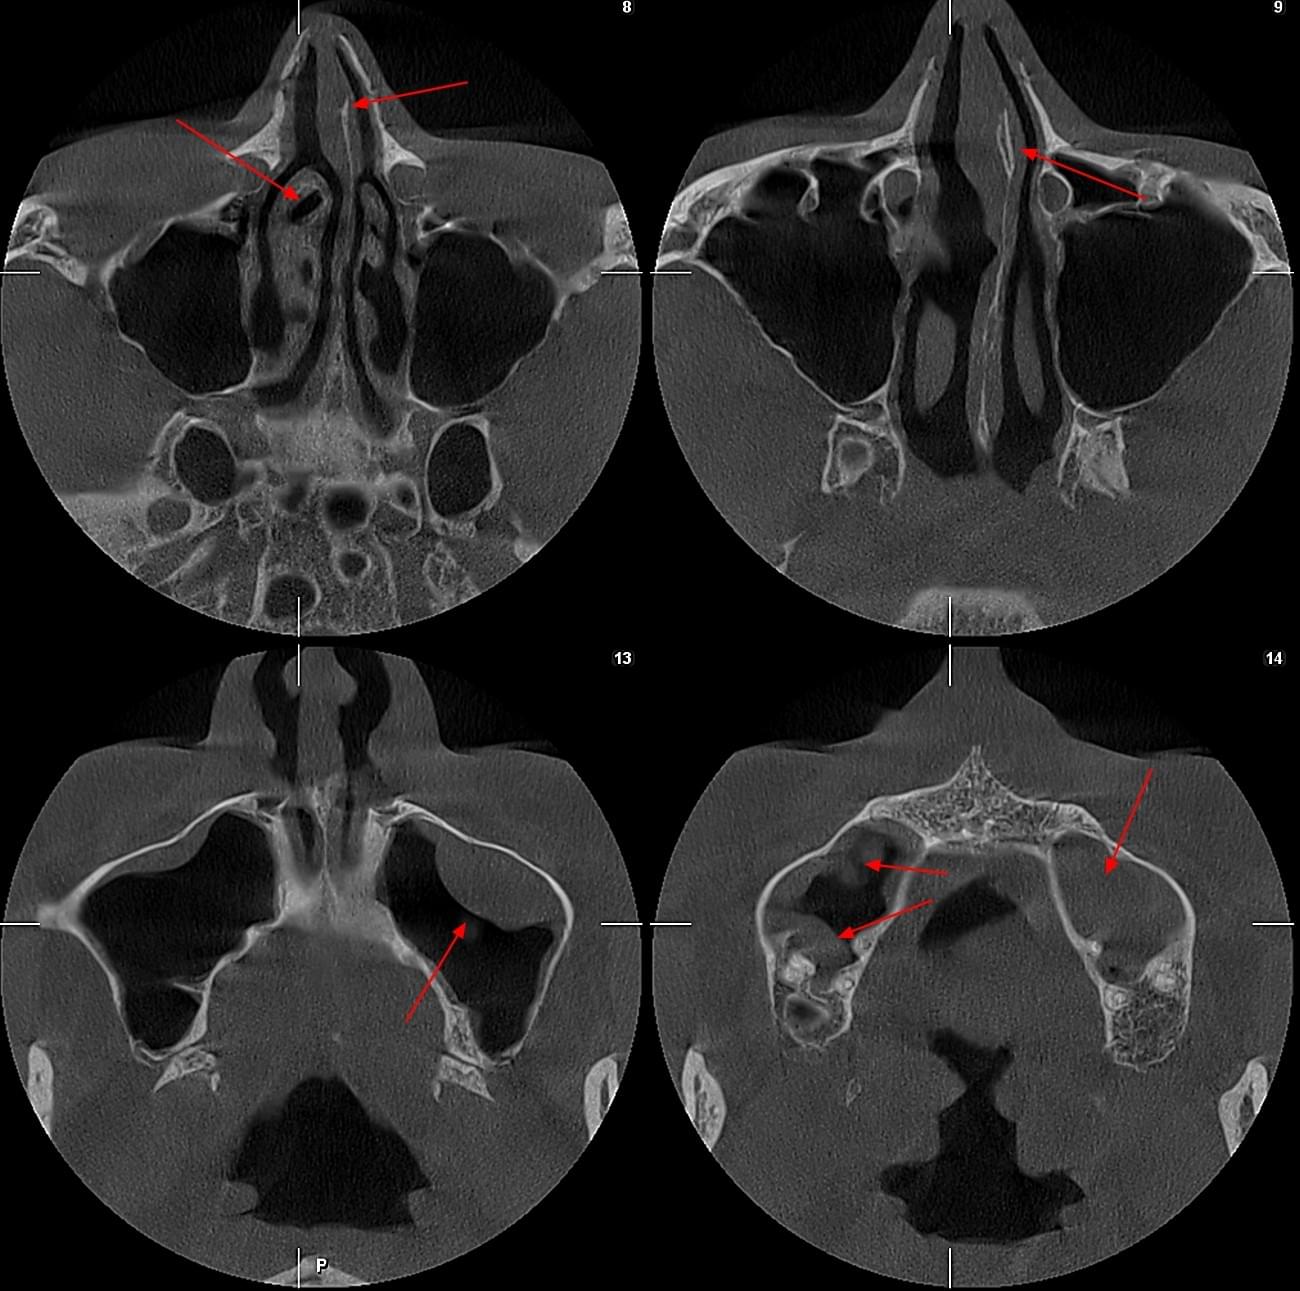

КПКТ (конусно-променева комп’ютерна томографія) — це 3D-знімок високої роздільної здатності. На відміну від звичайного рентгену, КТ показує:

У MyRayLab використовують сучасний апарат Planmeca 3D — доза опромінення всього 12 мкЗв (в 10–20 разів нижче, ніж у звичайних КТ), сканування 10 секунд, HD-якість.

ЛОР призначає обстеження у таких випадках:

КТ дозволяє провести віртуальну операцію: встановити імплант у програмі, виключивши будь-які ризики травмування пацієнта.